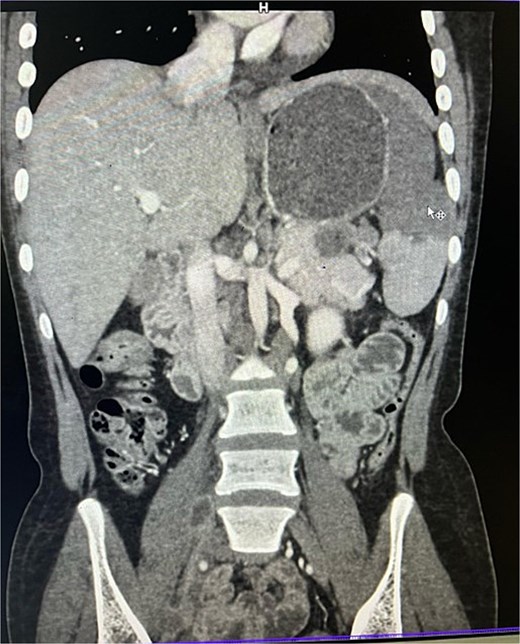

On imaging, ultrasonography showed a lobulated hypoechoic lesion in the region of the pancreatic tail and splenic hilum. This was very not conclusive, so a contrast-enhanced CT scan was planned, which revealed multiple necrotic, conglomerated lymph nodes (30 × 33 × 38 mm) near the splenic hilum and pancreatic tail, abutting the stomach and spleen, with maintained fat planes (Fig. 1). A splenic infarct involving a significant portion of the parenchyma was noted (Fig. 2), with multiple additional necrotic nodes along the retroperitoneum (paraaortic and iliac vessels) and mild pelvic free fluid. Then, CT-guided biopsy from the lymph nodal mass was planned, which showed moderately cellular smears showed caseous necrotic debris, lymphocytes, and clusters of epithelioid cells, suggestive of chronic necrotizing lesion consistent with TB.

Contrast enhanced computer tomography (CECT) abdomen showing necrotic lymph node mass near pancreatic tail and splenic hilum.